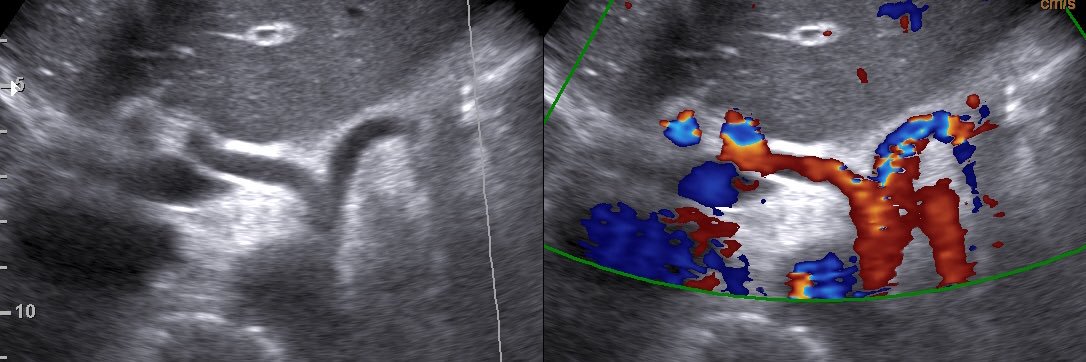

Comment on this lesion !! Diagnose 😱😱😱

#medico #ultrasoundeducation #ultrasounds #usg #ultrasoundtechnologist #cysts